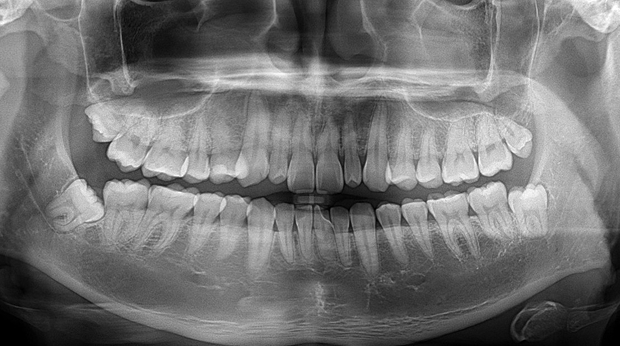

매복 사랑니 발치

임플란트와 사랑니 발치는 외과적 시술로 잇몸을 절개하는 외과적 시술은

짧으면 짧을 수록 시술 후 붓기와 통증이 최소화됩니다.

치과의사 경력 14년차 구강외과 전문의가 빠르고 안전하게, 아프지 않게 수술해 드립니다.